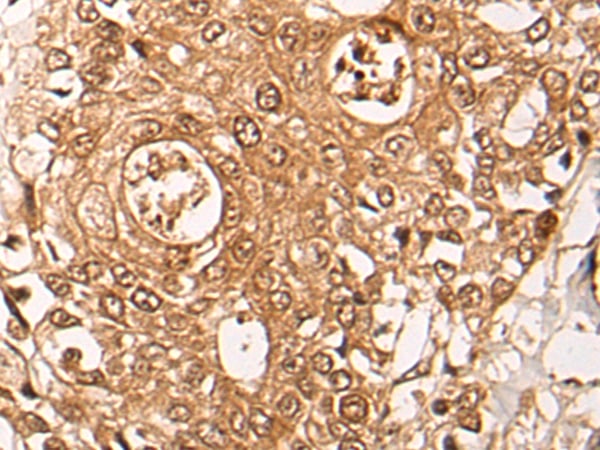

IHC (Immunohistochemisry)

(The image on the left is immunohistochemistry of paraffin-embedded Human prostate cancer tissue using 46722(ZPR1 Antibody) at dilution 1/40, on the right is treated with fusion protein. (Original magnification: x200))